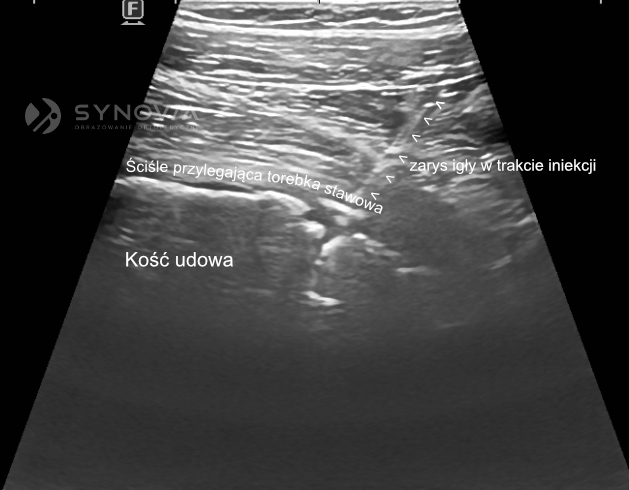

Precyzyjne umieszczenie preparatu w jamie stawowej ma kluczowe znaczenie dla efektu terapeutycznego. Preparat musi trafić dokładnie do wnętrza stawu, aby mógł wypełnić swoją funkcję.

Badania naukowe pokazują istotne różnice w skuteczności iniekcji wykonywanych „na ślepo” (bez kontroli obrazowej) w porównaniu z iniekcjami pod kontrolą ultrasonograficzną. W przypadku stawu biodrowego – jednego z trudniejszych do nakłucia – iniekcje wykonywane bez kontroli USG trafiają do właściwego miejsca tylko w około 60% przypadków. Oznacza to, że w pozostałych 40% przypadków preparat zostaje podany w niewłaściwe miejsce (np. do tkanek miękkich wokół stawu), co znacząco obniża lub całkowicie eliminuje efekt terapeutyczny.

Kontrola ultrasonograficzna wykonywana przez doświadczonego radiologa specjalizującego się w diagnostyce narządu ruchu zapewnia niemal 100% dokładność. Radiolog, którego podstawą pracy jest codzienna interpretacja obrazów USG różnych struktur anatomicznych, posiada szczególną wprawę w ocenie anatomii w czasie rzeczywistym. Ta specjalizacja przekłada się na umiejętność precyzyjnego prowadzenia i kontrolowania położenia igły oraz umiejętnego korygowania jej położenia. Osoba biegła w badaniach i iniekcjach USG może zmodyfikować technikę podania dopasowując się do potrzeb Pacjenta.

Dlaczego iniekcje powinny być wykonywane pod kontrolą USG?

Iniekcje pod kontrolą USG pozwalają jednoznacznie potwierdzić, że igła znajduje się wewnątrz jamy stawu. Ma to szczególne znaczenie w biodrze, gdzie „iniekcje na ślepo” często kończą się podaniem leku okołostawowo. USG zwiększa skuteczność terapii, zmniejsza ryzyko powikłań i pozwala dobrać optymalną drogę dostępu, omijając naczynia i struktury nerwowe.